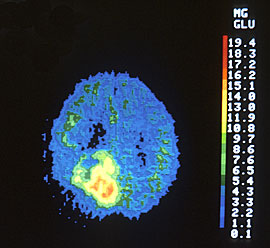

| PET (Positron Emission Tomography) Scan | |

Cancer cells’ high glucose consumption allows tumors of a certain size to be detected by a PET scan. This technique utilizes an imaging tool that picks up radio- active glucose injected into a patient. Since cancer cells produce more than half of their energy by glycolysis (break- down of glucose), they consume much more glucose than normal cells, and will therefore accumulate more radio- active material as illustrated in the picture below.